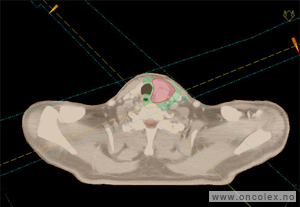

Legen(e) som skal undersøke deg hilser på deg før du sovner. Utenom anestesipersonellet og legen vil det vanligvis være 2 sykepleiere tilstede på stuen som hjelper deg og assisterer legen. Du skal legge opp beina i benholdere før du sovner for å sikre riktig liggestilling. Når du sover utfører legen undersøkelsen. Legen undersøker de ytre kjønnsorganene og kjenner på livmoren og eggstokkene med to fingre innvendig i skjeden og den andre hånden på magen. Skjedens innside og livmormunnen inspiseres ved hjelp av et spekulum. Spekelet holder skjedeveggene fra hverandre, for bedre innsyn. Ofte gjøres samtidig en ultralydundersøkelse via skjeden, for å få oversikt over livmor og eggstokk. I noen tilfeller undersøker legen urinblæren.

Ved ultralydundersøkelse føres en ultralydprobe inn i skjeden.